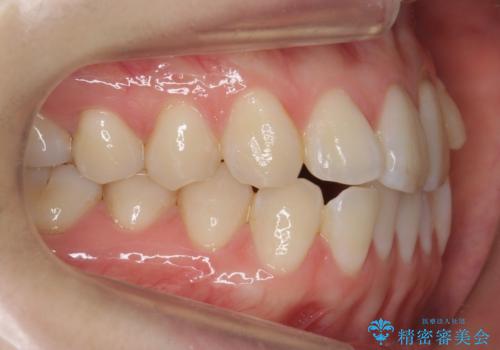

左上の前歯が飛び出しており、唇が笑った時に引っかかっていたのが解消しています。

左上の前歯は小さいため、(矮小歯)左右対称になるようにセラミックで形を修正する治療も併用しています。

歯を大きくかぶせるスペースを作るため、右上の奥歯を後ろに下げています。

左にずれていた上の正中も揃い、大変喜んでいただきました。